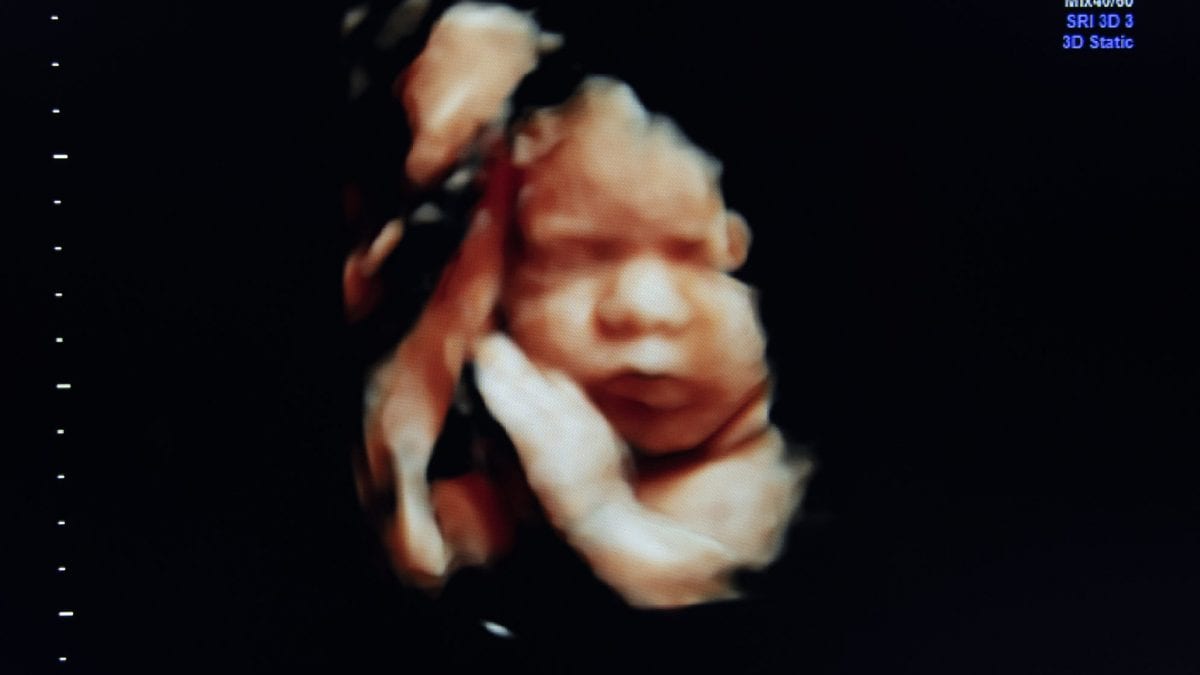

Arriva da Prato la prima ecografia tattile, che permetterà ai futuri genitori di poter toccare con mano il bimbo, anche se è ancora nel pancione. A brevettarla Stefano Brunetti, cieco da quando aveva 18 anni, per regalare anche alle persone non vedenti l'emozione della prima ecografia.

Anche solo immaginare di poter toccare con mano i lineamenti del proprio bambino, quando ancora è nel pancione, sembra qualcosa di impossibile. O meglio sembrava, prima che Stefano Brunetti, responsabile di un centro fisioterapico a Prato, brevettasse un’ecografia prodotta dalla stampante 3D.

Per dare vita a un'ecografia tattile bisogna rivolgersi, tra il quinto e il settimo mese di gravidanza, a un centro che sia dotato di un marchingegno in grado di fare un'ecografia Stl. In Italia sono più di 380 i centri sparsi sul territorio in grado di realizzare questo tipo di fotografia.

Solo questo genere di ecografia è infatti convertibile in un file che può essere spedito a una stampante 3D in grado di dare vita a una vera e propria scultura. La riproduzione del bimbo, ancora nel pancione, sarà poi tra le mani dei genitori in meno di 7 giorni, realizzata in un polimero vegetale, atossico, ecologico e per nulla dannoso.